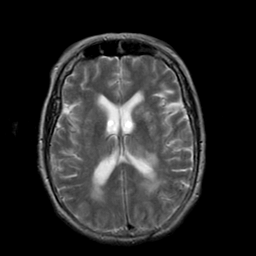

Stroke:T2-weighted MR #2 -- Slice #14

[Home][Help][Clinical] Slice 14